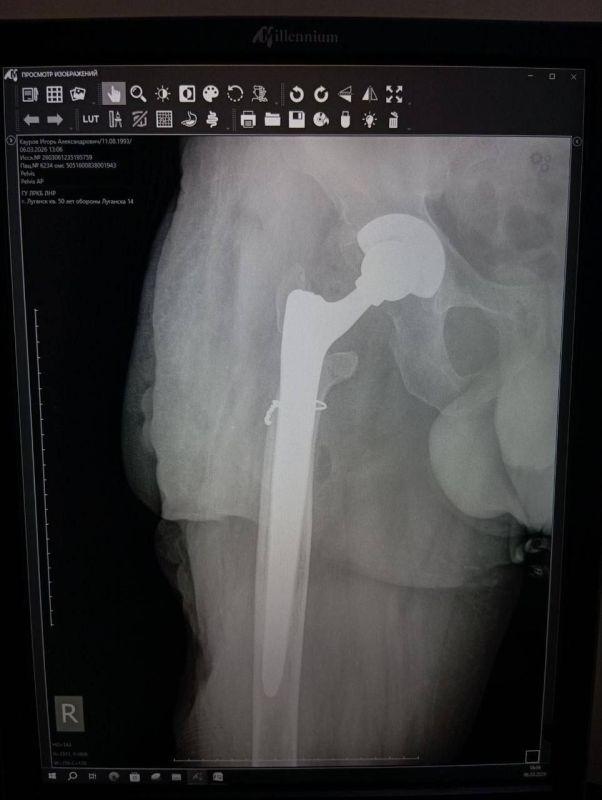

Уникальная операция в Луганской республиканской клинической больнице вернула ветерану специальной военной операции (СВО) возможность ходить без хромоты. Об этом сообщила министр здравоохранения ЛНР Наталия Пащенко. Руководитель Минздрава...

Об этом сообщила министр здравоохранения ЛНР Наталия Пащенко.Боец ушел на фронт 25 февраля 2022 года, прошел через горнило Херсонщины, а тяжелое ранение получил 28 августа.«Три с половиной года борьбы. Десять госпиталей. И одна операция, которая...

Уникальная операция в Луганской РКБ вернула ветерану СВО возможность ходить без хромотыТри с половиной года борьбы. Десять госпиталей. И одна операция, которая изменила всё.История сержанта из ЛНР, 1993 года рождения — это не просто медицинский отчёт....